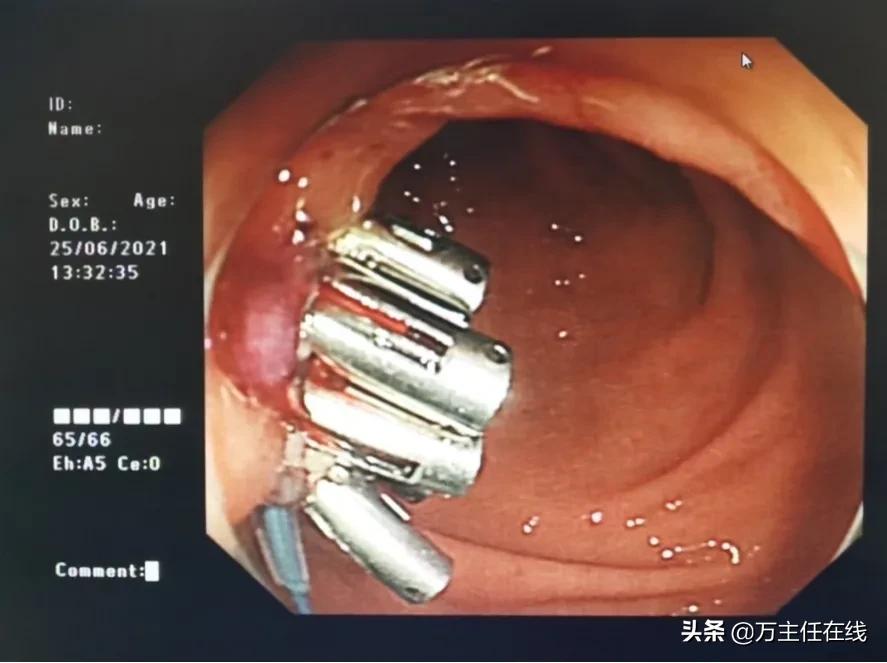

图表 2万荣医生团队正在手术中

图表 4完成手术,缝合胃窦切口

图表 5胃部切口缝合

在完善术前的相关检查后,消化内科万荣团队为陈女士进行了手术。手术进行非常顺利,成功为患者完成了双侧肝囊肿切除术。陈女士醒来后惊讶的发现自己竟无任何腹痛不适,看着自己完美无瑕的肚子,正如同手术路径所展示的那样,陈女士也在手术结束后露出了开心的笑容。